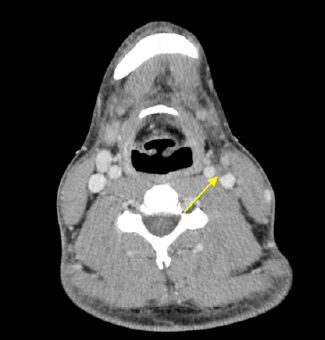

Lemierre’s Syndrome. Relevance of Ultrasound in Early Diagnosis

Julia Tejerina Puig, Manuel Jorge Marco Escoto, Fernando Asensio Payá and José María Carrasco Barea. 7(2): 31-34.